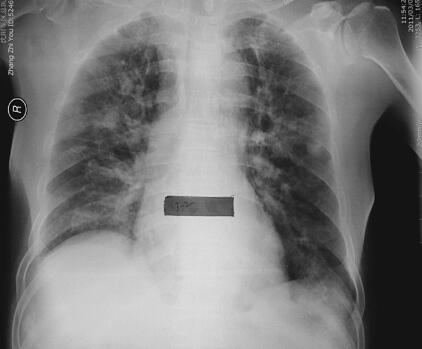

图2 入院第2天胸片:双肺渗出,右侧明显

患者,男性,87岁。急性起病,主因“劳累后胸闷、气短2天,加重伴咳嗽、咳痰1天”于2011年2月18日收入急诊监护室。患者于2011年2月16日劳累后出现胸闷、气短,伴咳嗽、咳黄痰,可平卧,偶有夜间憋醒,休息后症状缓解,翌日劳累后再次出现上述症状,无心前区疼痛,无发热、寒战,无恶心、呕吐,无尿少,就诊于笔者医院,进行心脏超声检查:EF 40%,冠心病、心肌梗死表现、心功能减低,考虑心尖部室壁瘤形成,二尖瓣、三尖瓣及主动脉瓣反流(轻度);腹部超声:双侧胸腔积液,少量心包积液;双肺CT(图1):双侧胸腔积液,心胸比例> 0.5;院第2天胸片见图2。血液分析:白细胞9.34×109/L,中性粒细胞85.5%;心肌酶谱:肌钙蛋白0.144μg/L,磷酸肌酸激酶125U/L,磷酸肌酸激酶同工酶20U/L;B型尿钠肽8326pg/ml。既往史:冠心病病史10余年,自服阿司匹林、复方丹参滴丸、硝酸异山梨醇酯等,2010年7月急性心肌梗死经内科治疗后病情稳定;陈旧性脑梗死病史10余年、胃部分切除史20余年。